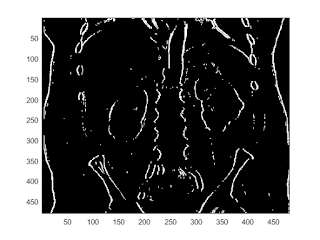

sobel edge filter

b = fspecial('sobel'); I2 = conv2(I,b,'same'); imagesc(I2); colorbar

imagesc(abs(I2)>200)